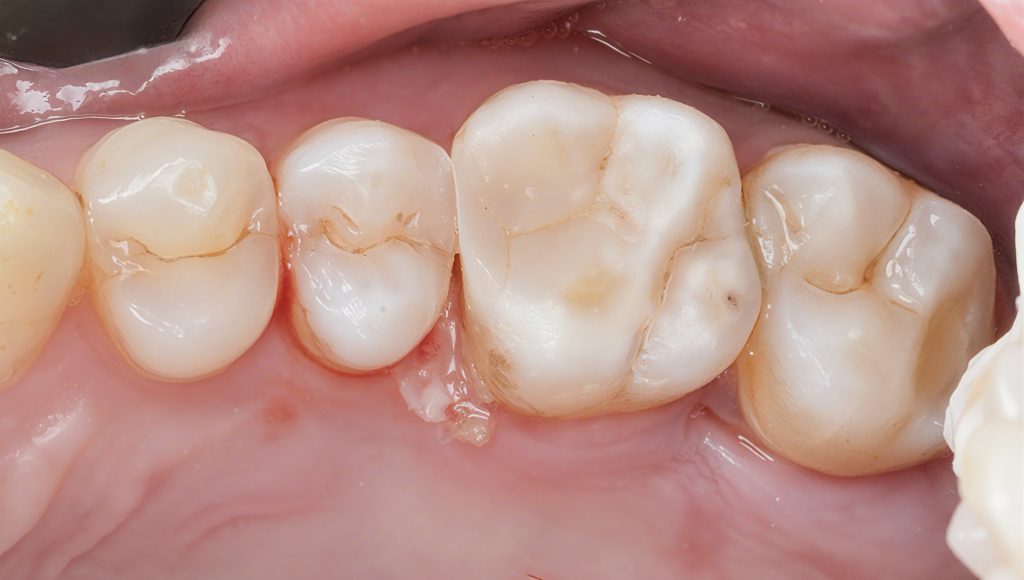

5. Layered Composite Build-Up

Composite was placed in controlled increments:

- 3M Filtek Easy Match Shades

For natural value and chroma blending.

- Tokuyama Estelite Ocher Stain

For fissure tinting and internal character.

- Anatomical build using small tipped instruments and brush adaptation.

7. Post-op Result

A clean, natural anatomy with:

- A sealed proximal contact

- Proper cusp-fossa relationship

- Smooth margins

- No postoperative sensitivity expected